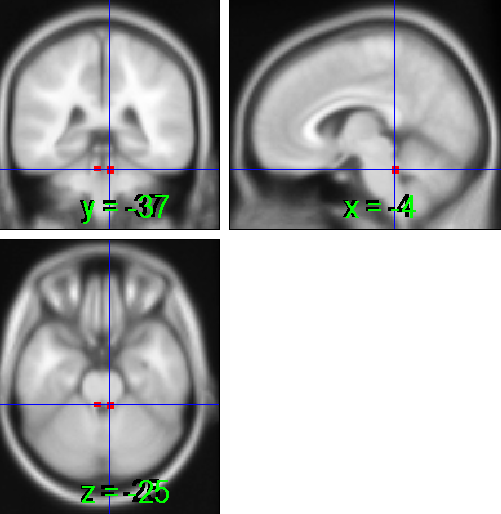

lc1